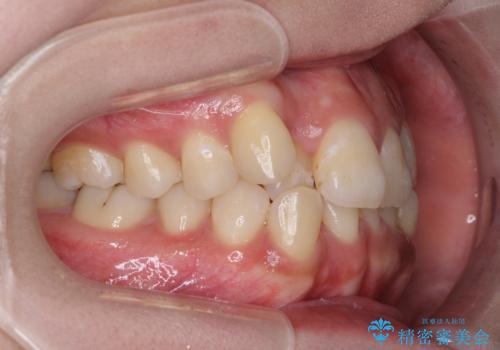

- 前歯のデコボコと残っている乳歯の部分へのインプラント治療を希望して来院された患者様です。

当初は目立たない上下裏側矯正を希望されていましたが、歯並びの悪さによる磨き残しが多く、歯肉炎が認められたため、より清潔な環境で治療を進められるインビザラインを選択することとしました。

前歯のデコボコが強かったため、上の奥歯を後方に動かす量が多くなり、結果として2年以上の治療期間を擁することとなりました。